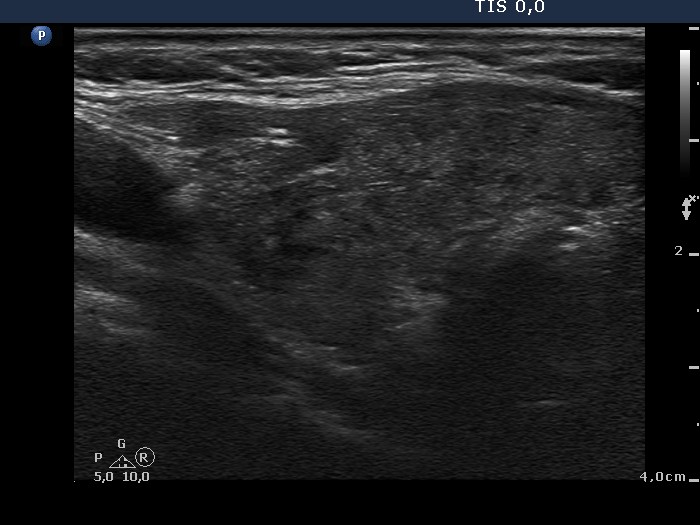

First examination (1st row of images):

Clinical presentation: a 63-year-old woman came to a yearly follow-up examination because of a known thyroid nodule and a hypothyroidism replaced with daily 75 microgram levo-tiroxine. She had neck discomfort She had neck discomfort while turning her head to the right.

Palpation : there was a nodule in the left lobe.

Hormonal investigation: indicated euthyroidism with TSH-level 1.01 mIU/L.

Ultrasonography: revealed hypoechogenic inhomogeneous thyroids. There was a hyperechogenic nodule in the left lobe. The nodule presented a halo sign and perinodular blood flow. It increased in size, therefore we performed aspiration cytology.Cytology: benign lesion.